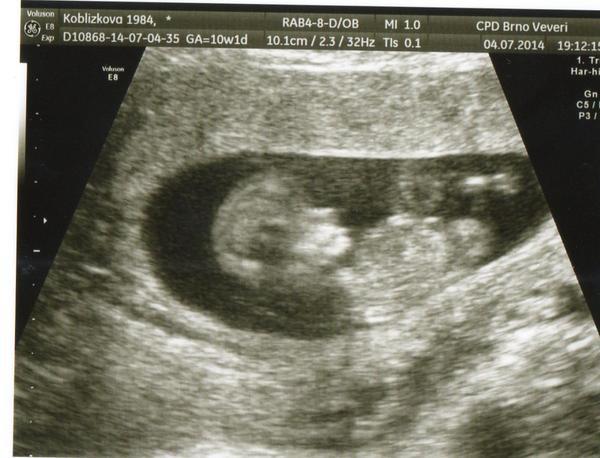

už to vidim 🙂 10+1tt 🙂 no ..... krásně holky ty vaše mimiiinka rostou

Furt bych na to koukala mít takhle krásou fotku ... hlavně Leni .... 12tt (skoro 13tt) za tebou a už to bude všechno jenom lepší ... !!! 😀

a pořád tlemim na tu fotku a říkám tomu malýmu že je to celá Lenička, že to uplně vidím 😀 ...ať už je to kluk nebo holka 😀